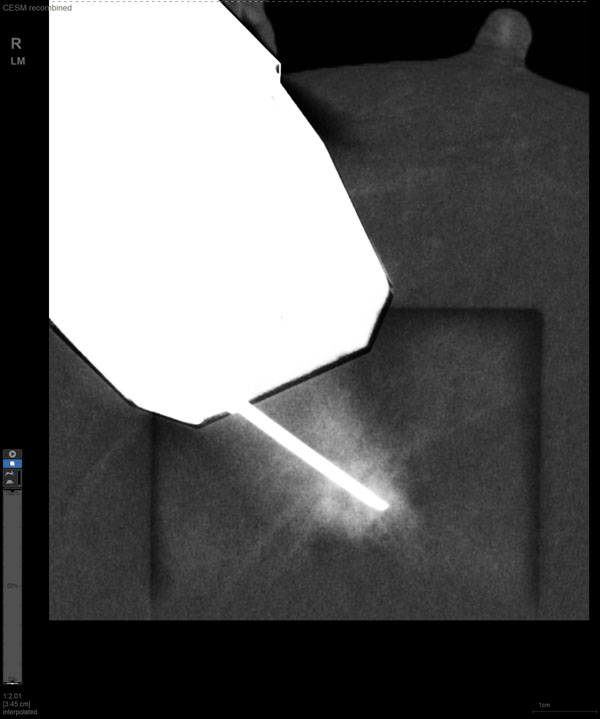

某患者增強磁共振成像MRI顯示腫瘤周邊有活性,中心區域有組織壞死。為得到準確的病理結果,穿刺靶區需避開腫物壞死區域。在與患者主管醫生充分討論后,放射科醫生為患者行CEM引導下穿刺活檢術。術中,CEM檢查腫物同樣顯示為環形強化,巧妙避開壞死區域后,穿刺靶區選擇了腫物增強早期明顯強化區域,術程順利,僅用時15分鐘。術后該患者病理結果為浸潤性導管癌Ⅱ級。